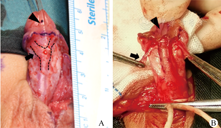

手术记录及取材均由同一主刀医生完成。阴茎脱套后观察尿道板周围海绵体的外观,测量其位于尿道海绵体分叉处两侧的海绵体宽度。取宽度平均值评估尿道板周围海绵体发育程度(图1)。取其中发育明显的一侧海绵体,在分离阴茎头翼过程中,取尖端组织(大小约0.2 cm×0.2 cm)进行组织学研究。

注:虚线部分为尿道板两侧尿道海绵体,箭头指示取材部位,三角形指示异位尿道口

术中观察尿道板周围尿道海绵体外观,多数远端型海绵体形态饱满、颜色鲜红,而多数近端型海绵体形态扁平,颜色苍白(图1)。海绵体的分叉点位于尿道开口近端,分叉后海绵体向远端走行于尿道板深面和两侧。通过比较海绵体分叉处平均宽度来判断海绵体发育情况,远端型尿道下裂尿道板两侧尿道海绵体宽度值为(0.36±0.12)cm,近端为(0.18±0.10)cm,远端型明显宽于近端型(P<0.05),说明远端型海绵体发育较好。